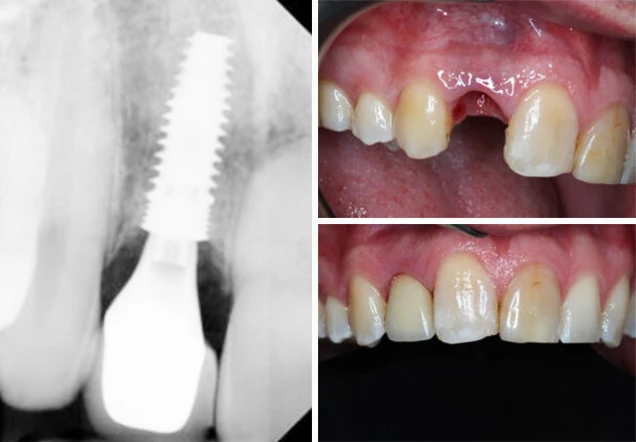

The patient presented with a split root in a front tooth. Dr. Login removed the tooth and completed an immediate implant placement.

Tooth Extraction & Implant Case

tooth extraction implant case